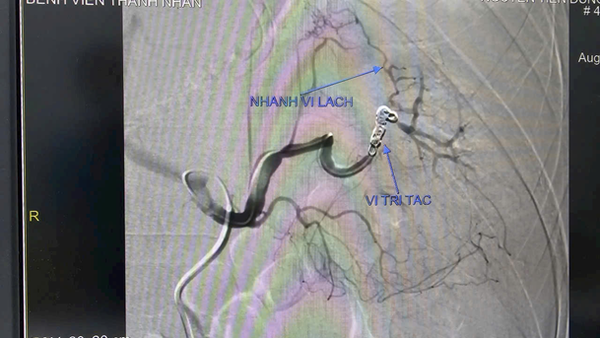

-    Sử dụng coil theo kỹ thuật “Sandwich” để nút tắc đoạn động mạch mang giả phình.

Kết quả sau can thiệp: ổ giả phình được bít tắc hoàn toàn, nhu mô lách vẫn được nuôi dưỡng nhờ hệ bàng hệ. Sau 24 giờ, tình trạng bệnh nhân ổn định, không còn dấu hiệu mất máu, dẫn lưu ổ bụng ra khoảng 2 lít máu cũ.